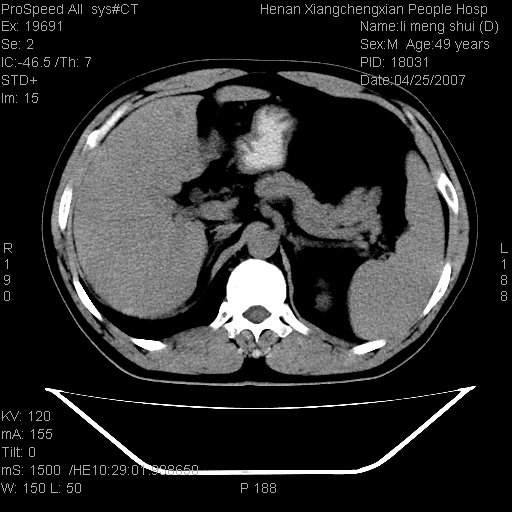

| 患者,男,49岁, 腹疼伴恶心\\呕吐20天,20天前无明显诱因出现右上腹部疼痛,钝疼,无放射,伴恶心\\呕吐,不伴发热.患者不愿增强. b超:肝脏右叶实性占位. ct:肝脏右叶可见一巨块状圆形低密度影,大小约93mm*84mm,其内可见点状高密度影,胆囊、胰腺、脾脏大小、形态及密度未见异常,腹膜后间隙未见肿大淋巴结影。 印象:肝脏右叶巨大肿块,性质待定,建议增强并穿刺活检进一步确诊。 ct平扫: ![]() ![]() ![]() ![]() ![]() ![]() ![]() ![]() ![]() ![]() ![]() ![]() ![]() ![]() ![]() ![]() ![]() 肝脏右叶肿块ct引导下穿刺活检术 患者于16时05分仰卧于ct检查台上,首先行肝脏ct扫描确定进针位置、深度、角度。在局麻下行ct引导下肝脏右叶肿块穿刺活检术。常规消毒、铺巾、局麻。在ct引导下使活检针经右侧腋中线、第9肋间隙垂直胸壁进针90mm,针头进入病变预定位置。在病变预定位置多点、多方向抽取小米样病变组织多块,涂片五张送病理检查。术后穿刺点局部无出血,未出现腹腔积液等并发症。术中及术后患者生命体征稳定,手术于17时10分成功完成。患者安返病房。 穿刺片 ![]() ![]() ![]() ![]() ![]() ![]() ![]() ![]() ![]() ![]() ![]() ![]() ![]() ![]() ![]() ![]() 病理结果肝细胞癌 ![]() 原贴地址:http://www.radinet.com.cn/forum_view.asp?forum_id=4&view_id=24130 ok |